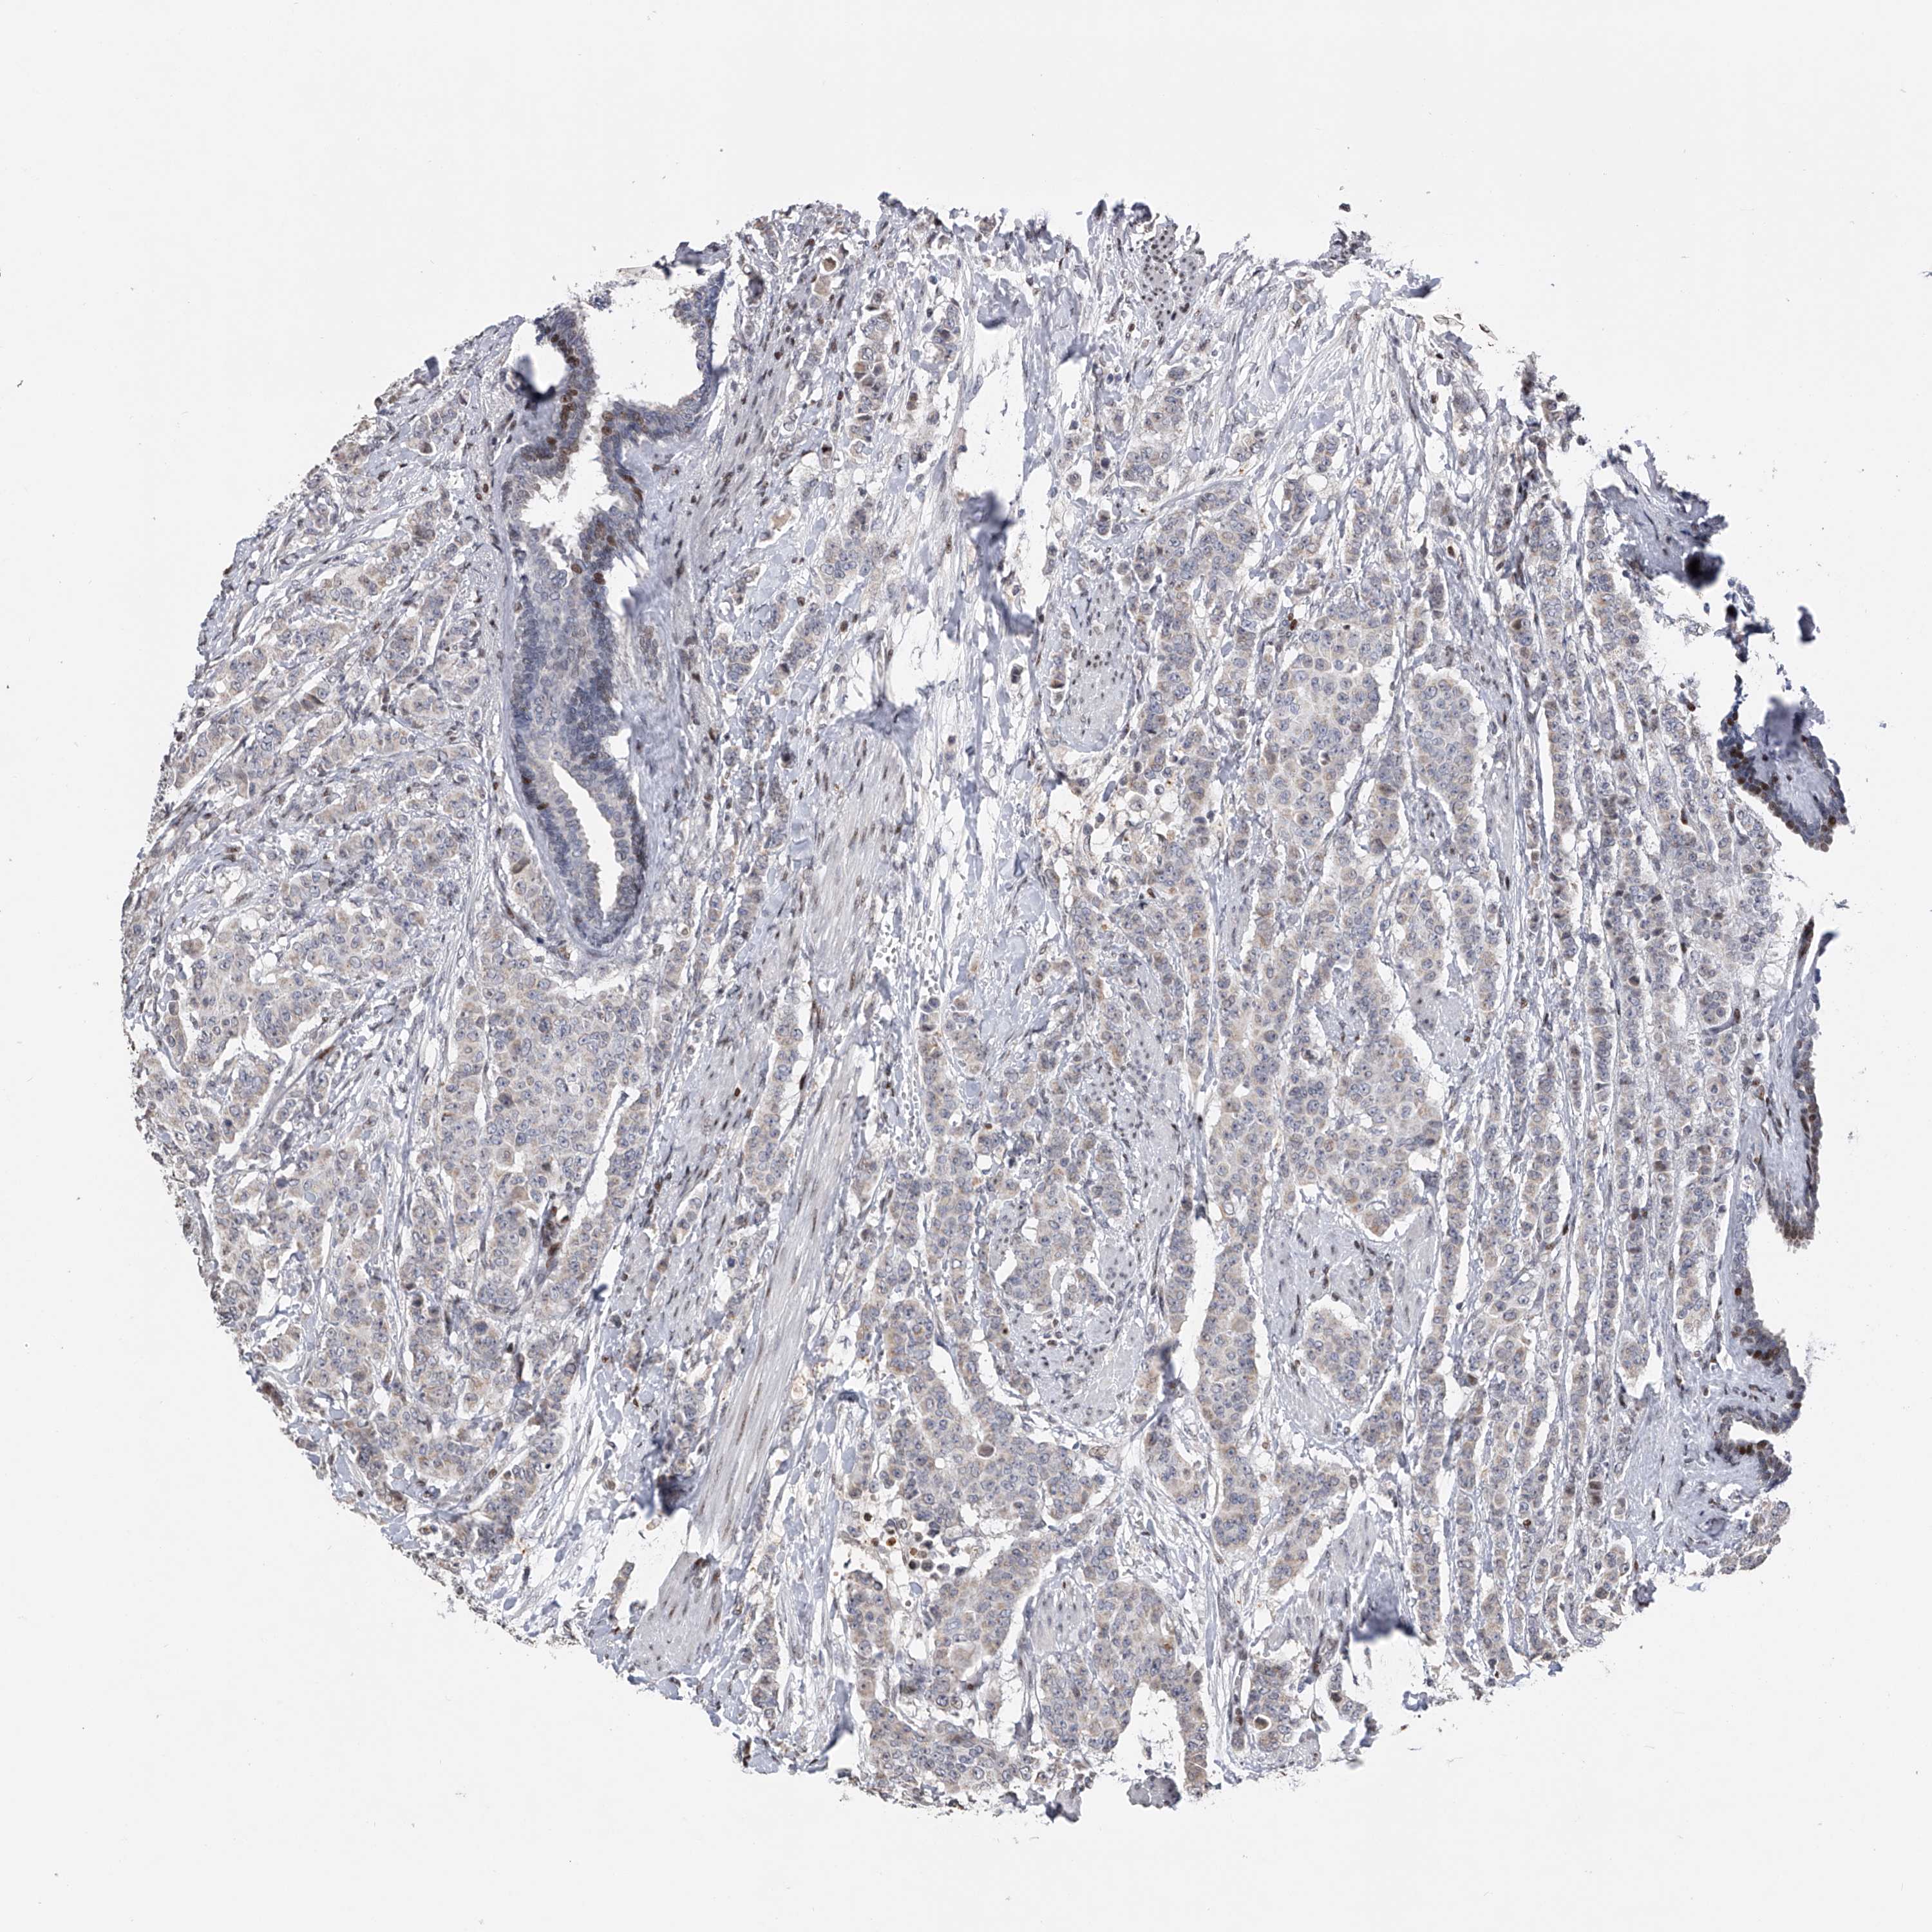

CANCER BREAST CANCER Show tissue menu

Breast cancer

Human cancer